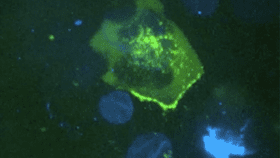

The team used a model of genital mucous membrane stored in a lab dish as a pretend "host" for the virus. Then, they recorded a T cell (a type of white blood cell) infected with neon green pigmented HIV as it made contact with the outer cells of the membrane, known as epithelial cells.

The infected T cell comes into contact with the epithelial cells and prepares to shed HIV particles.

When the infected T cell reached an epithelial cell, a pocket-type structure called a virological synapse formed. This allowed viral particles (the green dots in the video clip) to move between the infected and uninfected cells. They shoot out of the T cell a bit like rays out of a blaster gun, but – importantly – do not infect the epithelial cell. Instead, they travel beyond the cell to the macrophages (another type of white blood cell), which devour the HIV particles.

Virological synapse forms between the T cell and epithelial cell and HIV particles are shed.

The process takes an hour or two. At this point, the virus has been produced and shed and the infected T cell leaves to spread HIV to another cell.

Virus sheds and leaves.